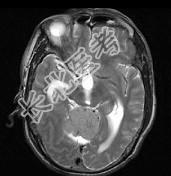

- 单项选择题男,61岁, 头晕头痛伴行走不稳1月余,请根据所提供图像, 诊断最有可能是 ( )

A、转移瘤

B、胶质瘤

C、淋巴瘤

D、髓母细胞瘤

E、(天幕切迹缘)脑膜瘤